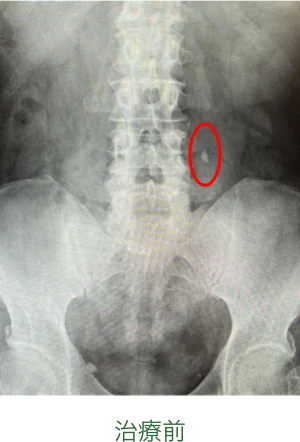

治療効果

一回の衝撃波治療により粉々に破砕され、後日結石が消失しています(赤で囲った部分)